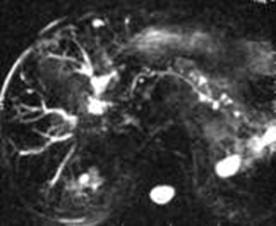

Рис 3 – 4. МРХПГ. Хронический панкреатит – сообщение кисты головки с вирзунговым протоком.